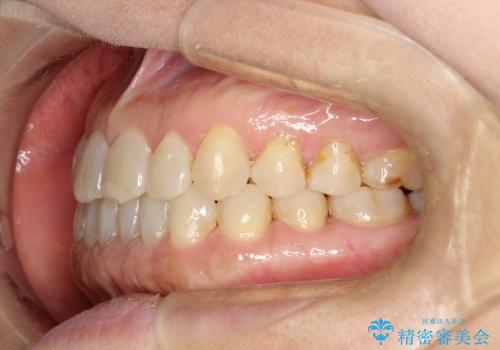

前歯の隙間 インビザラインによる目立たない成人矯正

- 前歯の隙間を気にされて来院されました。

インビザラインにて、目立たずに矯正治療を行うこととしました。

歯と歯の間にある隙間を閉じるのは、インビザラインでもしっかり治療できます。